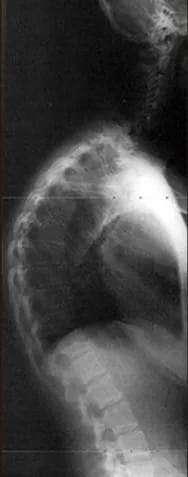

Kyphosis is an abnormal curvature of the spine. Your spine is supposed to curve in and out as it goes down your back to ensure your body is balanced, and everything lines up correctly. Curves that go outward are kyphotic; curves that go inward are lordotic. If you have kyphosis, it means your spine curves excessively outward. A normal kyphotic curve is somewhere between 20 and 50 degrees. Anything over 50 degrees would be kyphosis.